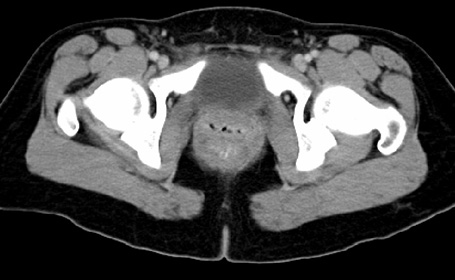

Obturator Internus

Urinary Bladder